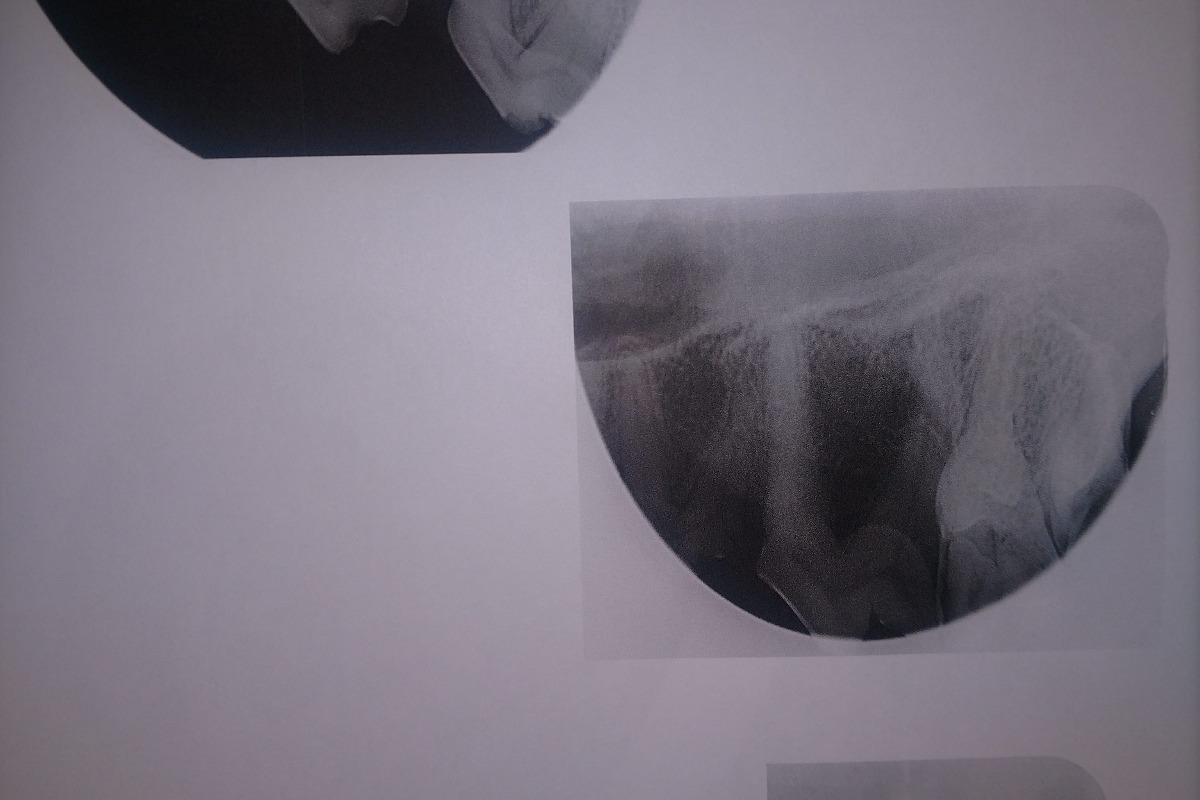

The following photos are her radiographs for anyone that knows how to read them, so you can see all the dead teeth that need future extractions, and some show the root canals:

The radiographs laid out a dim story of that long term damage: all 4 canine teeth were dead, 2 of those canines were broken off from the recent attempt on the gate; all of her lower incisors, and several molars on each side were also dead. The vet was surprised, in spite of massively evident wear and tear, that her upper incisors appeared to still be alive. More of her teeth were dead than live. However, there was some good news in that her gums were completely free of gum disease, she had very little plaque and tartar buildup, and that she hadn't lost any of the bone her teeth were seated in.

I had decisions to make. The surgeon could only work on 2 canines per day if I wanted to save them with root canals. Because 85% of jaw integrity rests on the roots of the lower canines, removing them would put her at a very increased risk to break her jaw in the future. With her having a clean mouth, she would be at a lower risk of infection following a dead and broken tooth into her jaw if I had just 2 root canals that day and waited on the rest of the work. Unfortunately, the broken canines (one upper and one lower) were on opposite sides, making them very difficult, if not impossible, to do the same day, as they would have to keep flipping her over at each step to get the opposite tooth.